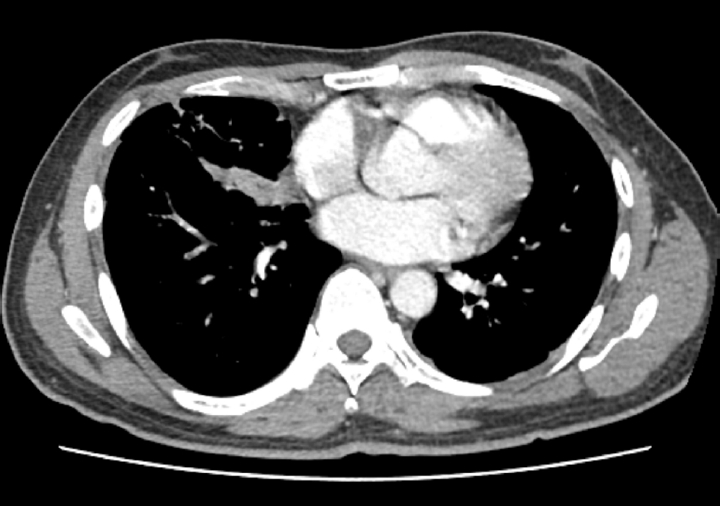

Upon admission, his vital signs were as follows: blood pressure, 100/60 mmHg; pulse rate, 120 beats/min; respiratory rate, 20 breaths/min; and body temperature, 38.2°C. Pulse oximetry revealed that oxygen saturation was 95% on room air. Chest auscultation revealed crackling rales in the lower bibasilar lobes. Initial laboratory investigations showed significant leukocytosis with white blood cell (WBC) count of 28,100 cells/µL and elevated C-reactive protein (CRP) level of 35.39 mg/dL. To evaluate for potential secondary infection, multiple microbiological cultures were performed during the early hospital course. These included blood and sputum cultures on the day of hospital admission (day 1), a follow-up sputum culture on day 2, and sputum and urine cultures on day 3. All cultures yielded no specific growth. Chest radiography revealed bilateral pleural effusions and patchy consolidations in both lower lung fields suggestive of pneumonia (Fig. 1). Contrast-enhanced computed tomography (CT) of the chest revealed ground-glass opacities in the right middle lobe, base of the right lower lobe, and left lower lobe, accompanied by intrinsic air and bronchovascular bundles. Based on these findings, the patient was admitted to the intensive care unit with a diagnosis of encapsulated necrotizing pneumonia.

Fig. 2.

Chest computed tomography on day 7 revealing multiloculated abscesses involving right middle and left lower lobes.

Fig. 2. Chest computed tomography on day 7 revealing multiloculated abscesses involving right middle and left lower lobes.